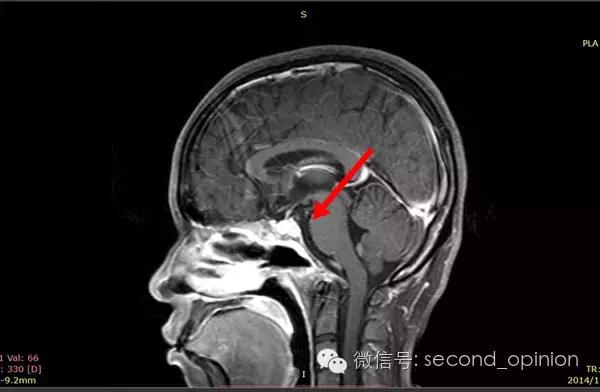

至2014年1月,出现左耳耳鸣,表现为低调杂音,未发现听力明显下降,偶有脸部麻木,无面瘫。行MRI检查,颅内占位范围约60*45*47mm。2014年2月2日第一次手术,行内镜导航下经蝶窦颅底肿瘤切除术,切除体积约50*45*50mm,手术顺利,术后头痛症状消失。左耳低调耳鸣术后消失两周后再次出现,右耳术后出现偶发轻度耳鸣。2014年5月4日第二次手术,行内镜口鼻蝶入路脊索瘤切除术,切除肿瘤体积45*40*50mm,过程顺利,术后耳鸣消失,病情稳定后出院。

2014年6月15日 进行射波刀放疗,32.5Gy/5fx,剂量曲线69%包绕,治疗期间对症脱水,减轻放疗反应,完成全部治疗后出院。

2014年12月 进行质子放射治疗。

日本国立癌症中心 2014年12月3日-12月31日

总剂量40GyE

2014年9月1日MRI(手术治疗前)

质子治疗前

2015年1月25日 对比质子治疗之前增强核磁共振影像无明显变化,脊索瘤放疗后变化缓慢,建议3月后继续复查。

2015年04月01日 对比增强核磁共振影像,同第一次复查。